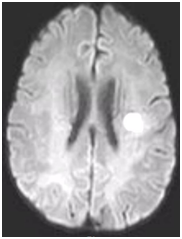

During follow-up in stroke clinic, her imaging was reviewed. MR imaging demonstrated large confluent areas of hyperintense T2 and FLAIR signal abnormality throughout the periventricular and deep white matter with extension into the subcortical white matter (Figure 1) (Figure 2). T1w images demonstrated low signal, corresponding to the T2/FLAIR abnormality on T2w images. This white matter abnormality is known as leukoaraiosis. The hyperintense T2/FLAIR signal abnormality also involved the anterior temporal lobes (Figure 3) (Figure 4) and external capsules (Figure 5) (Figure 6). This feature on MRI is uncharacteristic of other white matter diseases, notably the sporadic subcortical atherosclerotic encephalopathy. In our patient, the corpus callosum was spared. The lacunar infarcts were small vessel infarcts, typically seen in the deep white matter, basal ganglia, thalami, and the pons. On diffusion images, there was a small area of diffusion restriction in the left corona radiata that was consistent with an acute infarct (Figure 7) (Figure 8). Subsequently, there was an area of encephalomalacia on follow-up MRI at the location of the previous acute infarct. This abnormality correlated with the right-sided weakness seen prior to the index patient’s admission.

Figure 7 A small area of diffusion restriction in left frontal corona radiata consistent with an acute infarct.

Figure 8 A small area of diffusion restriction in left corona radiata in left frontal corona radiata consistent with an acute infarct.